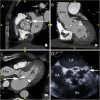

Infective Endocarditis (IE) remains a significant health challenge. Despite an increasing awareness, mortality is high and has remained largely unchanged over recent decades. Early diagnosis of IE is imperative and to assist clinicians several diagnostic criteria have been proposed. The best known are the Duke criteria. Originally published in 1994, these criteria have undergone significant modifications. This manuscript provides a timeline of the successive changes that have been made over the last 30 years. Changes which to a large degree have reflected both the evolving epidemiology of IE and the proliferation and increasing availability of advanced multi-modality imaging. Importantly, many of these changes now form part of societal guidelines for the diagnosis of IE. To provide validation for the incorporation of cardiac computed tomography (CT) in current guidelines, the manuscript demonstrates a spectrum of pictorial case studies that re-enforce the utility and growing importance of early cardiac CT in the diagnosis and treatment of suspected IE.